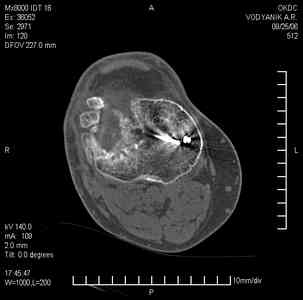

Уважаемые коллеги,В ортопедическое отделение обратился пациент: мужчина 47 лет, который в течение 4-х лет дваждыполучил травму костей, образующих правый коленный сустав. В 2002 v внутрисуставной оскольчатыйперелом проксимального метаэпифиза правой большеберцовой кости; в 2005 v внутрисуставнойоскольчатый перелом дистального метаэпифиза правой бедренной кости. В обоих случаях в разных лечебных учреждениях проводилось оперативное лечение переломов.При осмотре в отделении на основании результатов клинического осмотра и данных визуальныхметодов обследования поставлен диагноз:тугой ложный сустав дистальной трети правой бедренной кости, состояние после накостногоостеосинтеза перелома типа 33-В2.2 ; несросшийся перелом надколенника; неправильно сросшийсяперелом латерального мыщелка правой большеберцовой кости, состояние после металлоостеосинтезаперелома 41-В2.2; сочетанная осевая деформация правой ноги: варусная деформация правого бедра,вальгусная деформация правой голени; посттравматический артроз коленного сустава 4 ст по Kellgren-Lowrence; выраженное нарушение функции ходьбы и опоры. Внешний вид ноги больного, данные рентгенографического обследования и избирательно выделенные компьютерные томограммы приведены в приложении. В именах КТ использовано кодирование уровня по АО, т.е. _41, например, означает проксимальную треть голени.В отделении намечен v очень предварительно v следующий план лечения: 1. Иметь ввиду перспективу тотального эндопротезирования коленного сустава. 2. С учетом п.1 при проведении действий, направленных на устранение ложного сустава бедренной кости не использовать материалы, не подвергающиеся трансформации. 3. В ходе операции, направленной на устранение ложного сустава: А. удалить все металлоконструкции; Б. ревизовать зону пролежня под пластиной на бедре, при наличии признаков достаточной жизнеспособности кости выполнить остеопериостальную декортикацию, дрилинг ложа пластины; В. Удалить рубцовую ткань по плоскости ложного сустава, и в пространстве между костными форагментами, насечь обращенные друг к другу поверхности. Ввести штифт с блокированием (например Stryker с учетом особенностей расположения дистальных блокирующих винтов у этойконструкции). Осуществить остеосинтез с учтанением варусной деформации бедренной кости. Пространство в зоне ложного сустава и пустоты в метафизе бедренной кости заполнить резорбирующимся цементом на основе гидроксиапатита кальция. Для дистальной фиксации использовать винты с переменным шагом резьбы. Вариант:, винты вводить после заполнения метафиза цементом. Дополнительные виды создания межфрагментарной компрессии во встречно-боковом направлении обсуждаются. Г. Быть готовым к кровопотере. Д. Учесть высокий риск инфекции, тромбоэмболических осложнений. Е. Вопрос о внешней иммобилизации решить по результатам оценки стабильности остеосинтеза. Вариант - одноосевой стержневой аппарат для шунтирования гвоздя с модулем на голени и дистракцией коленного сустава в течение 3-5 недель. Просим вашей критики намеченного плана и конструктивных предложений. С уважением к сообществу, Ординатор В.С. Саплин

Движения приличные, есть за что бороться. Такая ротация голени кнаружи, если она действительно есть (для уточнения можно сделать КТ на уровне обоих метафизов и бедреных, и берцовых ксотей, не меняя положение ног во время съемки), большого значения не имеет. А уж на фоне всего остального тут - вообще говорить не о чем.